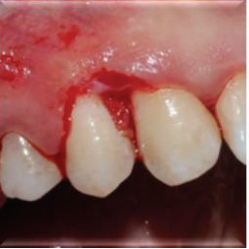

计划切除增生牙龈。由于增生范围较大,拟利用腭侧牙龈进行软组织修复。